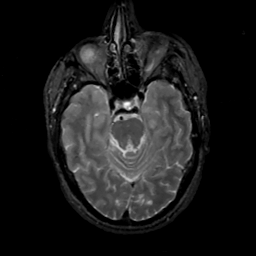

MR Study #14, June 2, 1991 -- Slice #17